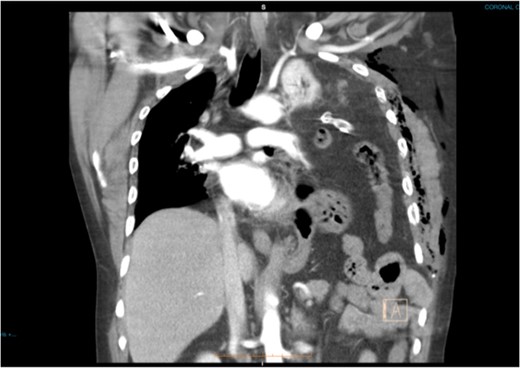

A 47-year-old male was brought to the Emergency department by ambulance after a high speed motor vehicle accident. On arrival, he had a Glasgow Coma Scale of 13, a patent airway with cervical spine collar in situ, spontaneous tachypnoeic breathing with an oxygen saturation of 97% on 15 l of oxygen. He had unequal breath sounds with decreased air entry on the left. He was tachycardic with a blood pressure of 110/70 mmHg. There were multiple bruises and abrasions to his torso and bilateral lower limbs. He had no previous medical history and was otherwise healthy. Initial chest x-ray was suspicious for a left-sided haemopneumothorax (Fig. 1) and an intercostal chest tube (ICCT) was inserted to the left side with a repeat x-ray confirming its position. However, there was minimal drain output and little swing. Subsequent computed tomography (CT) scan of the chest detected a left diaphragm rupture with a large diaphragmatic hernia where most of the left thorax was replaced by intra-abdominal contents (Fig. 2). A decision was made for emergency laparotomy to repair the diaphragmatic hernia. The patient was intubated in the emergency department prior to transfer to the operating theatre. While no ventilation problems were noted during transfer, the patient’s abdomen was seen to become progressively more distended to a point where it became tight and tympanic on percussion (Fig. 3). An underlying lung injury was suspected and the cardiothoracic team was called. At laparotomy, a significant pneumoperitoneum was confirmed with sudden escape of air upon entering the peritoneal cavity. The large hernia containing spleen, stomach and small bowel was reduced and the posterolateral diaphragmatic defect was repaired with a non-absorbable suture. This was followed by a left thoracotomy that identified a superficial laceration in the left upper lobe of the lung which was repaired with Prolene sutures and re-enforced with tissue glue. The patient was then transferred to the intensive care unit in a stable condition and made a good recovery. It is likely that the lung injury was caused secondary to intercostal catheter insertion during resuscitation in the Emergency Department. However, it could also have been secondary to associated left rib fractures or blunt trauma during the accident.

Coronal CT slide showing the entire left haemithorax being replaced by abdominal contents. Note the subcutaneous emphysema post ICCT insertion.